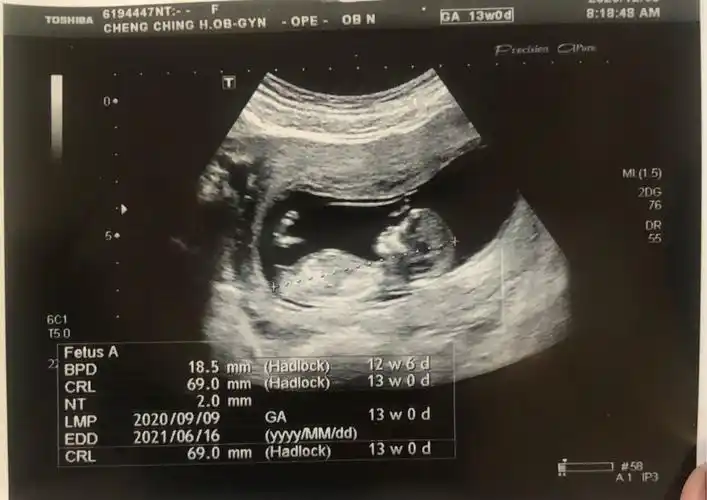

这是快十二周做的nt !这个亮点是不是说宝宝是男孩的记录大啊?

13周nt图脊柱弯着就是男孩这种说法准吗

13周nt归来,有没有懂nub理论的姐妹帮看男女呢?

已生男孩的nt单子是什么样